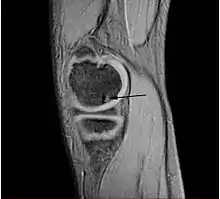

يمكن استخدام الأشعة السينية أو الأشعة المقطعية أو التصوير بالرنين المغناطيسي لتشخيص ما إذ كان المريض يعاني من التهاب العظم والغضروف السالخ، فهي تظهر نخر العظم تحت الغضروف أو تشكل شظايا رخوة أو كلاهما،[25] وفي بعض الأحيان تستخدم أشعة الطب النووي العظمي لتقييم درجة الترخي داخل المفصل.[26]

ويصنف تطور المرض في مراحل، هنالك نوعان رئيسيان من التصنيف مستخدم: يحدد واحد منهما عن طريق التشخيص بالتصوير بالرنين المغناطيسي بينما يحدد الأخر عن طريق التنظير، ومع ذلك تمثل كلا المرحلتين التقدم الطبيعي للحالة المرضية من مرض (التهاب العظم والغضروف السالخ)، في حين يعد التصنيف بالمنظار في العظام والغضاريف المعيار كما صنف اندروسون التصوير بالرنين المغناطيسي هو الشكل الرئيسي المستخدم في هذا المقال [29]، وتعد المرحلتين الأولى والثانية مراحل مرضية مستقرة، بينما هنالك مراحل مصنفة تعد غير مستقرة الا وهي المرحلتان الثالثة والرابعة التي تسمح للسائل الغضروفي والسائل الزليلي ان يكون بين الأجزاء والعظام.

'مرحلة أندرسون التصوير بالرنين المغناطيسي للكشف عن مرض التهاب العظام السالخ (التهاب عظمي غضروفي)' [30]